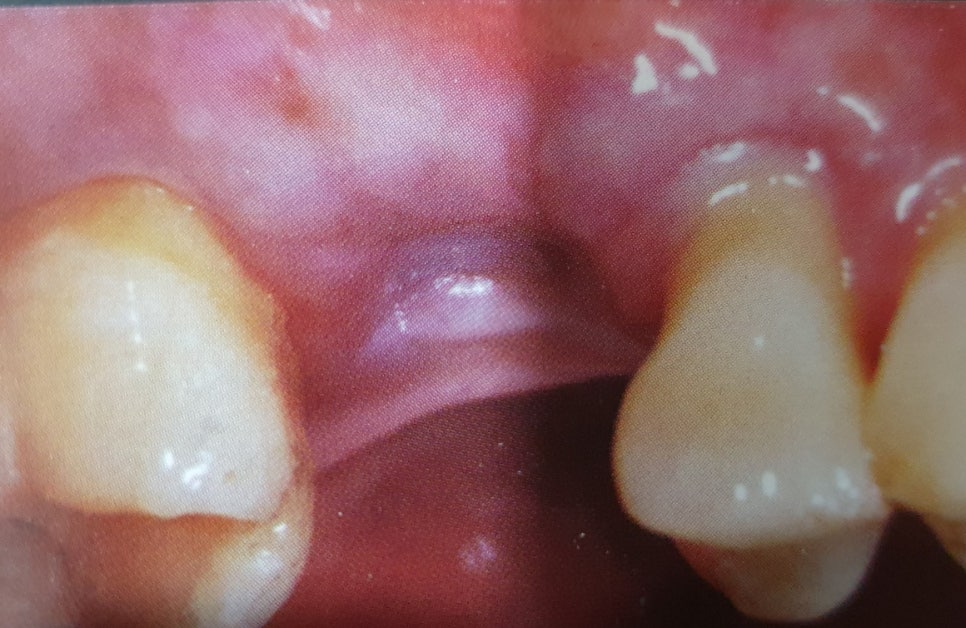

파노라마 사진과 CT상 큰 문제가 없고 잇몸뼈 상태가 임플란트를 식립하기에 적합하면

치과에 내원한 바로 당일에도 위의 사진처럼 신논현역치과 중 임플란트 잘하는 스마일뷰치과에서 임플란트 식립이 가능합니다.